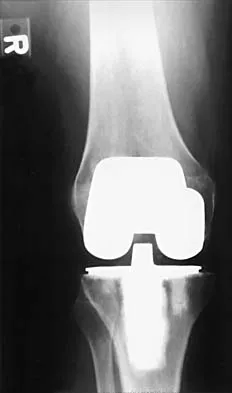

Question 42

Figure 9 shows the AP radiograph of a 65-year-old man who has knee pain and swelling. What is the most likely diagnosis?

Explanation

Although all the choices are known causes of joint degeneration (secondary osteoarthritis), only chondrocalcinosis shows distinct linear calcification of the cartilage due to deposition of calcium pyrophosphate crystals. Gout is a recurrent acute arthritis resulting from the deposition of monosodium urate from supersaturated hyperuricemic body fluids. Hemochromotosis is characterized by focal or generalized deposition of iron within body tissues. Arthritis may be present but is less common than other manifestations such as liver cirrhosis, skin pigmentation, diabetes mellitus, and cardiac disease. Rheumatoid arthritis is a nonspecific, usually symmetric inflammation of peripheral joints resulting in destruction of articular and periarticular structures. Ochronosis is a hereditary enzyme deficiency (homogentisic acid oxidase) resulting in deposition of homogentisic acid polymers in articular cartilage. Barrack RL, Booth RE Jr, Lonner JH, et al (eds): Orthopaedic Knowledge Update: Hip and Knee Reconstruction 3. Rosemont, IL, American Academy of Orthopaedic Surgeons, 2006, p 188.